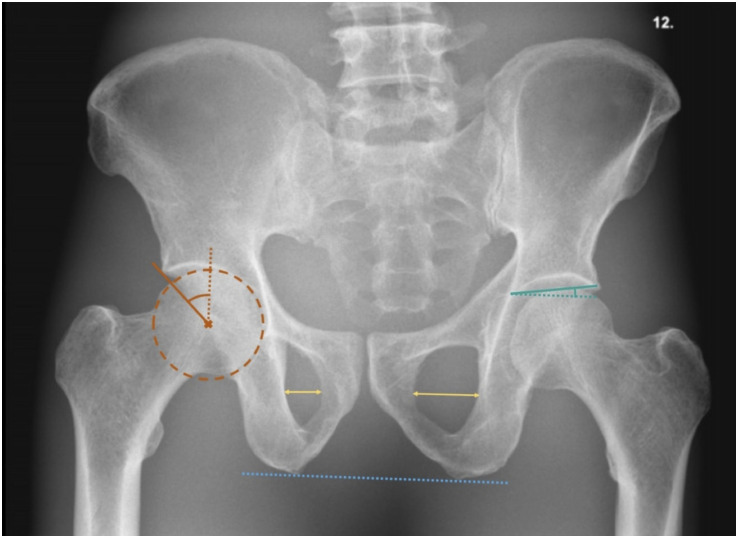

Purpose: To estimate agreement between measurements of lateral center edge angle (LCEA) and acetabular inclination angle (AIA) made, respectively, on Computed Tomography (CT) scans by humans and radiographs analyzed by an algorithm. To estimate impact of pelvic rotation on agreement between CT and radiographic measurements.

Abstract Image

Results: Mean measured bias (95% confidence interval [CI]) between CT and radiographs for LCEA of right/left hip was 5.53° (95% CI: 4.81 to 6.24) and 5.13 (95% CI: 4.43 to 5.83), respectively. Corresponding values for right/left AIA were 1.08 (95% CI: 0.49 to 1.67) and -0.03 (95% CI: -0.60 to 0.05). Pelvic rotation affected right LCEA and AIA measurements, with a change in obturator foramen index of, respectively, 0.35 and 0.6 resulting in approximately 2° change in values.